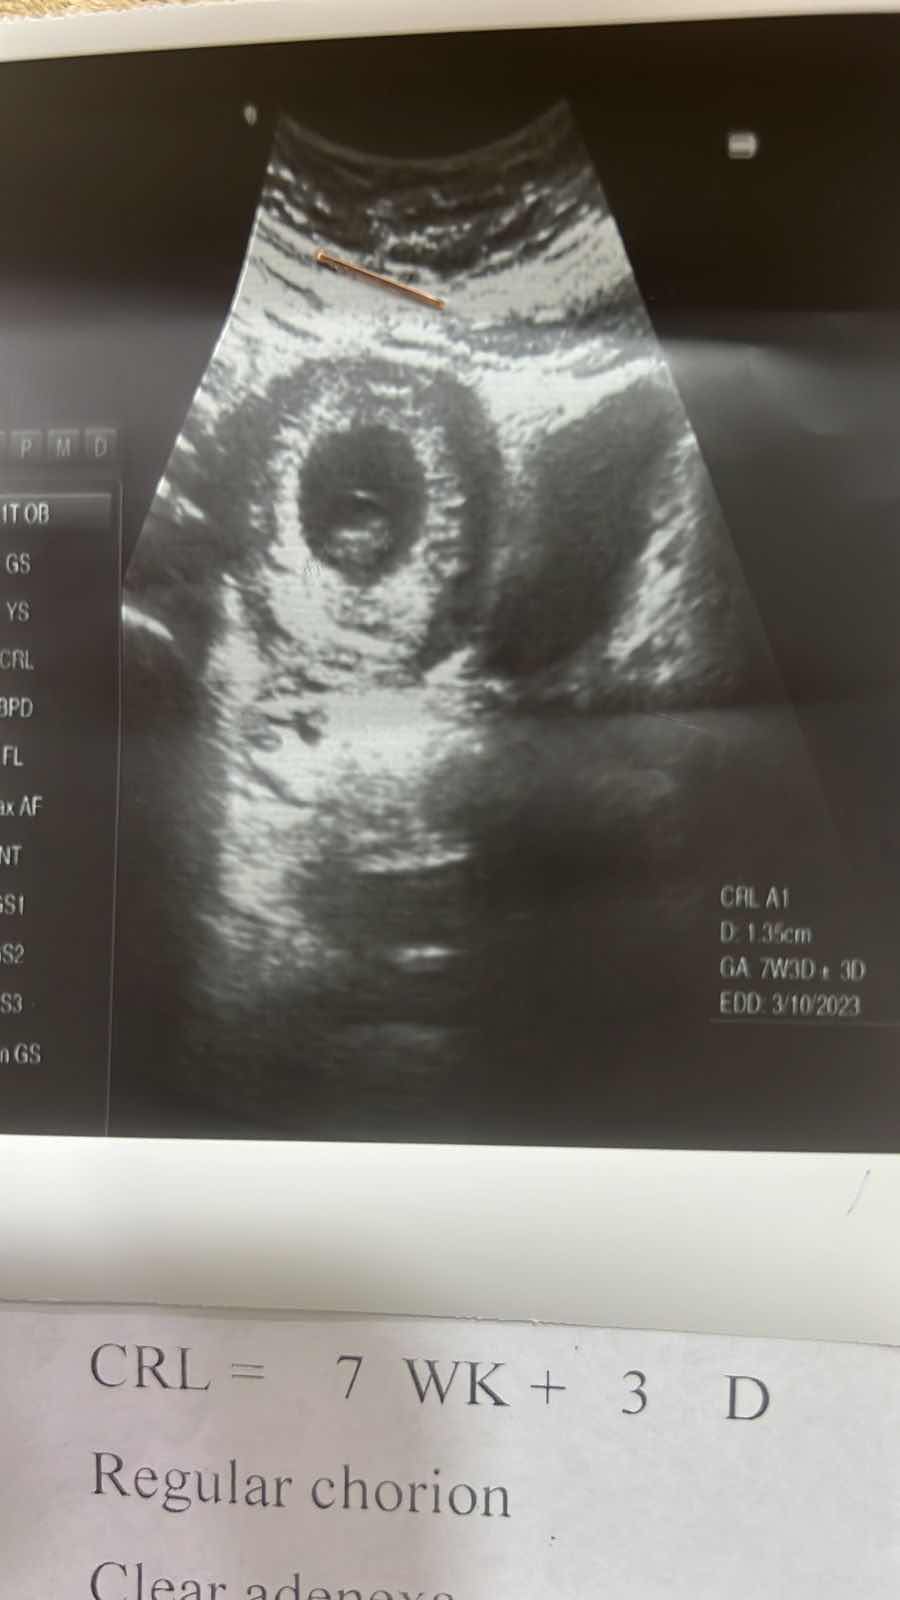

كشف جنس الجنين بعمر ٧ اسابيع

مرحبا ممكن تشوفون الي جنس الجنين واكون ممنونة الكم

بهذا العمر للجنين من المستحيل ولا بأدق الأجهزة معرفة جنسه 0 2022-07-26T10:59:39+00:00

بهذا العمر للجنين من المستحيل ولا بأدق الأجهزة معرفة جنسه